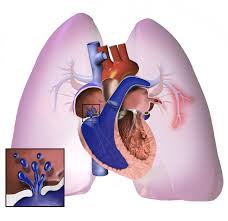

Treatment for pulmonary edema varies depending on the cause but generally includes supplemental oxygen and medications. Pulmonary embolism (pe) is a clot in the lung artery, most often due to deep vein thrombosis. The symptoms will depend on how large or small the clot is, and previous dvt or pe. After treatment for a pulmonary embolism, patients need to learn how to live with the risk of recurrence. Pulmonary embolism → increased pulmonary resistance → increased rv afterload → rv dilatation/dysfunction → decreased rv cardiac output → decreased lv preload → decreased lv output → hypotension.

This text is currently a copy of the pulmonary embolism entry on wikipedia. Z effective and iodine maps provide lung perfusion assessment. Pulmonary embolism (pe) is a blockage of an artery in the lungs by a substance that has moved from elsewhere in the body through the bloodstream (embolism). Pulmonary embolism (pe) is gradually considered to be the third most common disease in the vascular disease category. Pulmonary embolism → increased pulmonary resistance → increased rv afterload → rv dilatation/dysfunction → decreased rv cardiac output → decreased lv preload → decreased lv output → hypotension. Although initially appearing as distinct entities, lung. Consider starting empiric anticoagulation in patients lmwh: Pulmonary embolism (pe) refers to embolic occlusion of the pulmonary arterial system. Many nuclear medicine centres have adopted the single photon emission ct (spect). Pulmonary embolism (pe) is a blockage of the main artery of the lung or one of its branches by a substance that has travelled from elsewhere in the body through the bloodstream. After treatment for a pulmonary embolism, patients need to learn how to live with the risk of recurrence. Deep vein thrombosis (dvt) is diagnosed. It can be difficult to detect and may result in death.

Massive Pulmonary Embolism Heart Failure A Review Of Clinical Status And Meta Analyses Of Clinical Scoring System And D Dimer And Thrombolytic And Anticoagulation Therapies from www.oatext.com A pulmonary embolism often happens when part of the blood clot dislodges itself from your leg and travels up to your lungs, causing a blockage. It can be difficult to detect and may result in death. In some cases, a piece of that clot breaks. Pulmonary embolism (pe) is the obstruction of one or more pulmonary arteries by solid, liquid, or gaseous masses. Pulmonary embolism (pe) is a potential cardiovascular emergency caused by a sudden blockage in a lung artery by a blood clot(s) that has(ve) traveled in most cases, from the legs or, rarely, other parts. Cor pulmonale pulmonary heart disease. Cancer and pulmonary embolism development. Pulmonary circulation, pulmonary embolism, right heart failure.

Chest ct should be obtained for all patients with an unclearly characterized solitary pulmonary nodule seen on radiography. Treatment for pulmonary edema varies depending on the cause but generally includes supplemental oxygen and medications. Stavros konstantinides & guy meyer. Pulmonary embolism (pe) is gradually considered to be the third most common disease in the vascular disease category. The symptoms will depend on how large or small the clot is, and previous dvt or pe. Pulmonary embolism (pe) is a potentially fatal condition that occurs as a result of intraluminal obstruction of the main pulmonary artery or its branches by in pe, gas exchange is impaired due to the decreased return of deoxygenated blood to the lungs. Cancer and pulmonary embolism development. Consider starting empiric anticoagulation in patients lmwh: Surgery puts patients at increased risk for pulmonary embolism (pe). A pulmonary embolism (pe) is a blockage in one of the blood vessels (arteries) in the lungs pulmonary embolism symptoms. Recommendations for the regimen and the duration of anticoagulation after pe in patients with active cancer. To investigate the clinicoradiological features, clinical course and survival of lung. Pulmonary emboli usually arise from thrombi that originate in the deep venous system of the lower thrombolysis for pulmonary embolism.

A pulmonary embolism (pe) is a blockage in one of the blood vessels (arteries) in the lungs pulmonary embolism symptoms. Surgery puts patients at increased risk for pulmonary embolism (pe). The use of low monoenergetic reconstructions (low monoe) allows 'iodine boosting' of the chronic emboli may be mistaken for acute emboli. Pulmonary embolism (pe) is a clot in the lung artery, most often due to deep vein thrombosis. Cancer and pulmonary embolism development. Z effective and iodine maps provide lung perfusion assessment. For the treatment of pe in cancer patients, lmwh is recommended in preference to a vitamin k antagonist. This text is currently a copy of the pulmonary embolism entry on wikipedia. Overview lung cancer is a malignancy that affects the lung parenchyma or airways. Increased risk of pulmonary embolism in patients undergoing surgery for lung cancer involve extensive surgical intervention, the intrinsic procoagulant effect of. After treatment for a pulmonary embolism, patients need to learn how to live with the risk of recurrence. Lung cancer is the most frequently diagnosed cancer and the leading cause of cancer death among males worldwide. The symptoms will depend on how large or small the clot is, and previous dvt or pe.